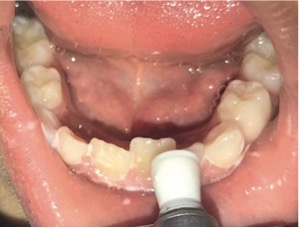

Se realizó la profilaxis de los dientes a ser extraídos (Figura 4) utilizando pasta profiláctica para remoción del biofilm presente en la estructura dentaria, posteriormente, antisepsia intraoral con clorhexidina 0,12% y extraoral con iodopovidona tópico, evitando posibles contaminaciones por microorganismos. En seguida, se seco la mucosa, y fue aplicado anestésico tópico en gel de benzocaína durante 3 minutos. Se realizó con anestesia terminal infiltrativa (Figuras 5 e 6) y el bloqueo del nervio incisivo con aguja corta y clorhidrato de lidocaína 2% con epinefrina 1:100.000, respetando la dosis máxima de dos tubos y medio.

Figura 4: Profilaxis previa a la exodoncia